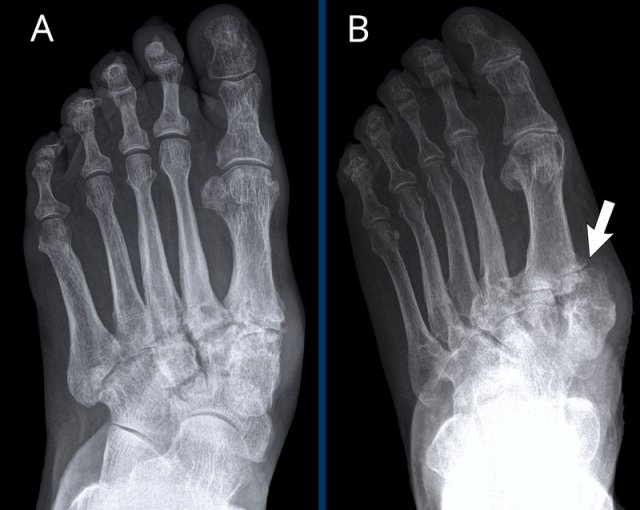

Rheumatoid arthritis in the feet Rheumatoid arthritis in the feet

In this case of rheumatoid arthritis there are marginal erosions adjacent to almost all MTP joints (arrowheads).

The 5th MTP joint is most frequently involved in  rheumatoid arthritis.

When erosions are as severe as in this case, it can look like pencil-in-cup deformity (white arrow) as is frequently seen in psoriatic arthritis.

However, the primarily affected MTP joints distribution and less affected interphalangeal joints is the clue that this is a case of rheumatoid arthritis.